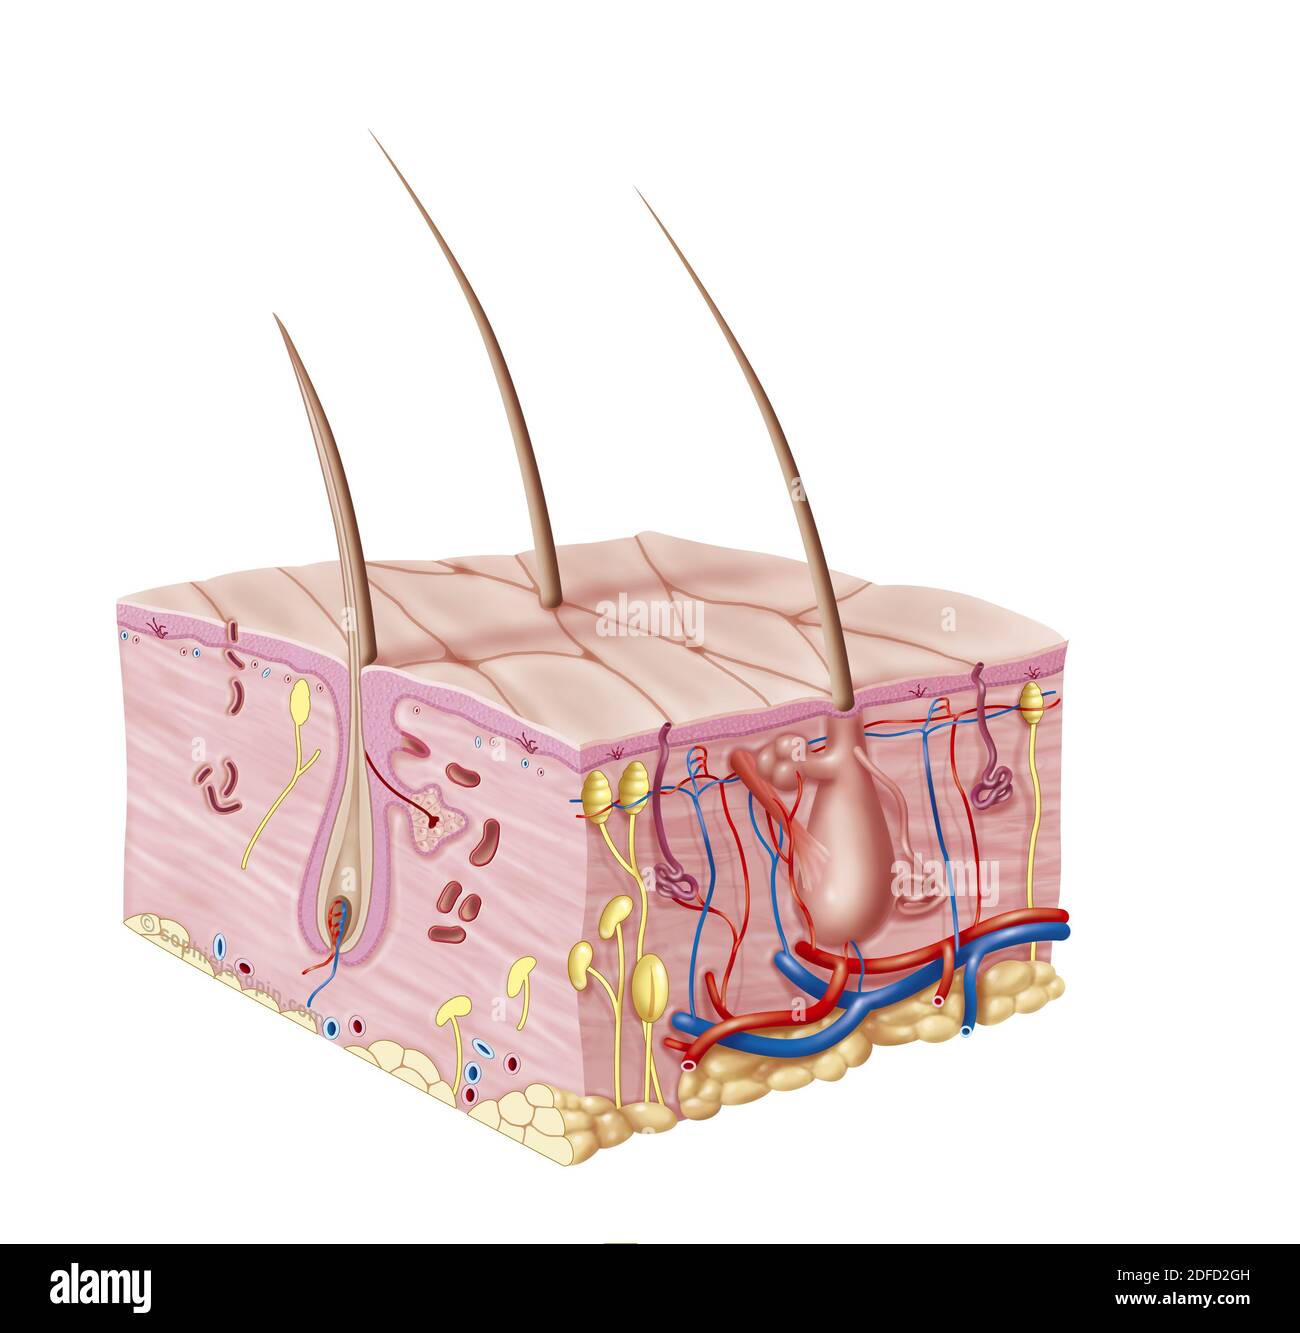

Baby-pediatric skin cut Stock Photohttps://www.alamy.com/image-license-details/?v=1https://www.alamy.com/baby-pediatric-skin-cut-image388135345.html

Baby-pediatric skin cut Stock Photohttps://www.alamy.com/image-license-details/?v=1https://www.alamy.com/baby-pediatric-skin-cut-image388135345.htmlRM2DFD2GH–Baby-pediatric skin cut